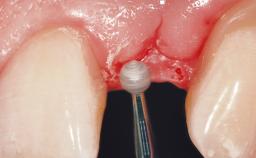

A 42-year-old female patient was referred to our clinic at the School of Dentistry of the University of São Paulo in November 2004, presenting a deficient restoration in the upper left central incisor. The clinical examination revealed no gingival retraction or any signs of gingival inflammation and, therefore, previous periodontal treatment was not considered. The patient presented a high lip line at full smile and a thin tissue biotype. This combination characterized a high-risk situation from an anatomic point of view, which required careful preoperative planning and cautious surgical execution.

Loading Protocol Immediate

Provisional Implant-Supported Prosthesis Prosthodontic margin < 3 mm apical to mucosal margin Prosthodontic margin < 3 mm apical to mucosal margin

Soft Tissue Contour and Volume Ideal